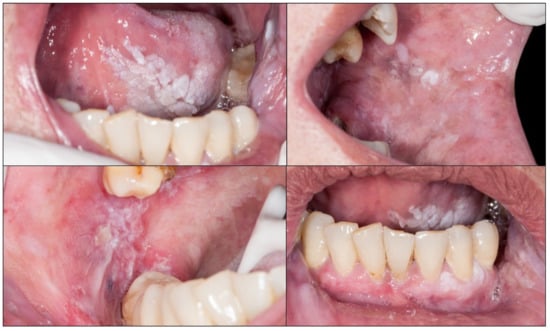

4.1. Clinical Signs of Early Oral Carcinoma and Oral Lesions at Risk of Developing Cancer—Oral Potentially Malignant Disorders (OPMD)